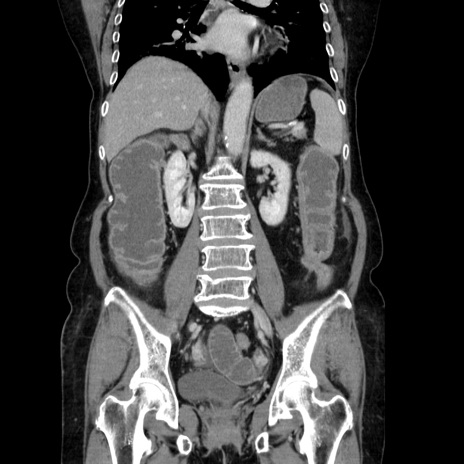

症例5(冠状断像)

【症例】70歳代女性

【主訴】お腹が張る

【現病歴】1週間くらい前から腹部膨満の自覚あり。昨日夜から増悪したため、本日救急外来受診。

【身体所見】意識清明、BT 36.5℃、BP 165/106mmHg、HR 80bpm、SpO2 98%、腹部:膨満、軟、自発痛・圧痛なし、触診にて不快感あり、腸蠕動音:減弱

【データ】WBC 12600、CRP 1.04

横断像